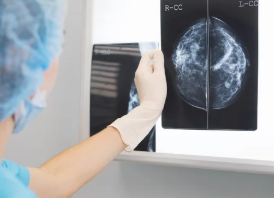

2. 유방촬영 판독 결과지 보는 법

촬영 후 며칠 내에 병원 또는 건강검진센터에서 판독 결과지를 받을 수 있으며,

가장 핵심적인 부분은 **"BI-RADS 등급"**과 "소견"입니다.

📌 BI-RADS 등급 (미국방사선의학회 표준 등급 분류)